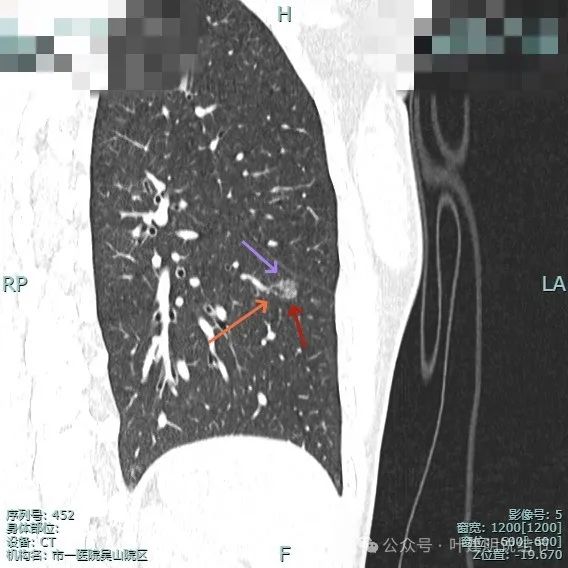

再看主要病灶的靶重建情况:

左侧病灶10:

病灶表面不平有分叶与凹凸,密度也不均匀,有点状实性成分,邻近胸膜(叶间裂)。

表面有毛刺,灶内有小空泡征,边缘毛糙不平,密度显得不均匀。

部分边缘有毛刺或小棘突,病灶边上有扩张的细支气管,整体内部密度欠均匀。

边缘毛糙,血管进入,灶内密度显得杂乱。

有扭曲的血管进入血管,表面有凹陷与分叶。

密度不太纯,表面不平,血管有异常增粗。

胸膜有轻微牵拉,表面不平,多处微小血管进入,整体密度显得不匀。

血管征明显、灶内小空泡征、胸膜牵拉、边缘细毛刺征。

整体看上去密度不均、边缘不平、灶内空泡征以及细毛刺征均明显。